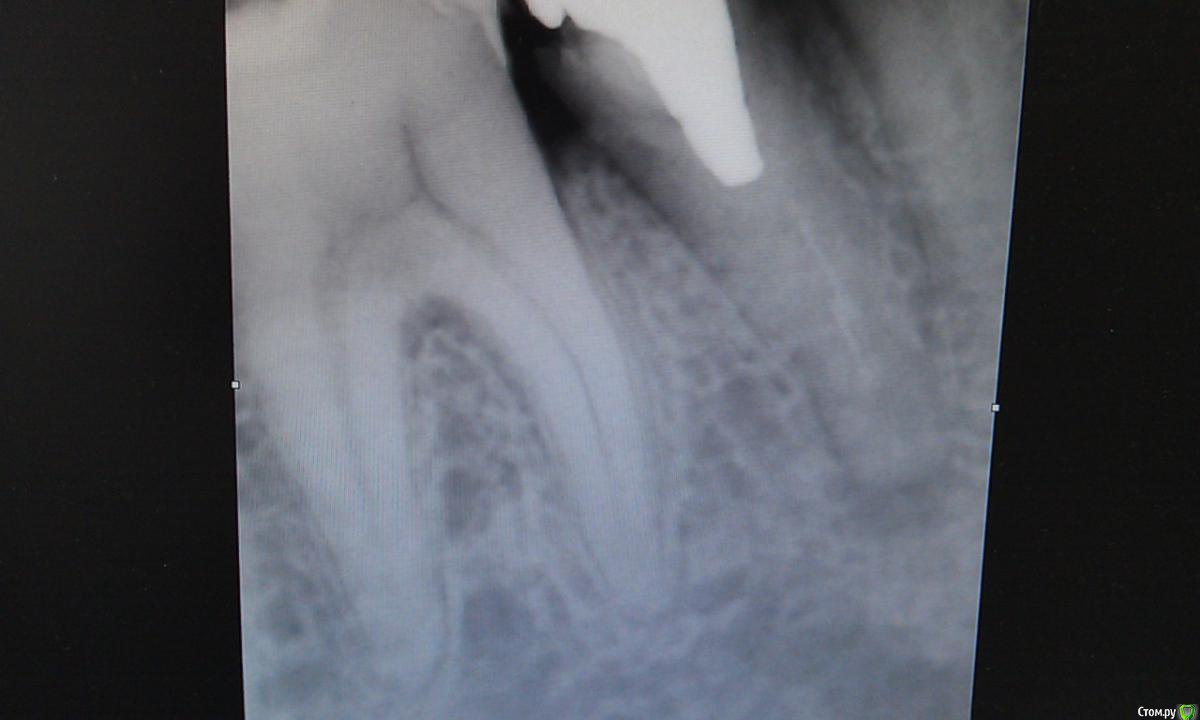

Валерия482 Опубликовано 12 мая, 2015 Поделиться Опубликовано 12 мая, 2015 Я человек очень далекий от стоматологии, по этому могу допускать ошибки в терминологии=)Ситуация:есть корень с культиевой вкладкой и коронкой на ней(металлокерамика), живу с этой конструкцией около 12 лет. 08.05.15 десна у корня отекла, появилась чувствительность зуба при прикусывании.10.05.15 появилась небольшая подвижность зуба, отек десны уменьшился.1 стоматолог (08.05) изучив снимок (на руках отсутствует) порекомендовал: удалить коронку, высверлить вкладку (успех 50 х 50), пролечить периодантит и далее в обратном порядке.2 стоматолог (12.05) изучив снимок (фото снимка прилагаются) вынес вердикт "удалять".Я на распутье, т.к. не могу решить что же делать.Помогите пожалуйста советом.Спасибо! Ссылка на комментарий

Гарриевич Опубликовано 13 мая, 2015 Поделиться Опубликовано 13 мая, 2015 + за перелечиваниевкладка короткая, извлечь ее будет достаточно просто Ссылка на комментарий